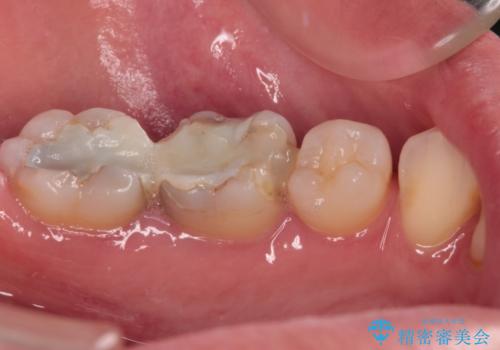

- 奥歯のむし歯処置を行っていたものの、しみて痛みが続く状態での経過観察が続いていたため、転院を希望して来院された患者様です。

痛みが続いているとのことで、むし歯が神経組織に及んでいる可能性があるため、処置を行うに当たりラバーダムによる唾液の排除を行うこととしました。

手前の歯はむし歯の範囲が広いためオールセラミッククラウンにて、最後方歯は部分的なむし歯であったのでPGAインレー(プラチナゴールドインレー)にて治療を進めることとしました。